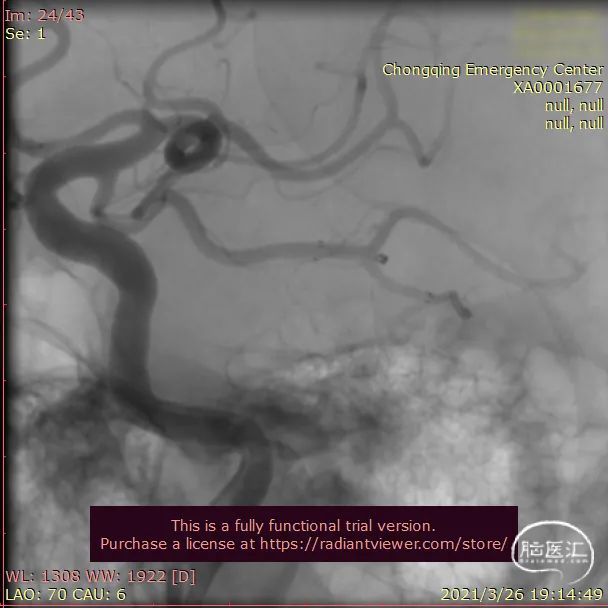

术前影像DSA、DSA 3D

送入3.0mm*15mmNeuroform Atlas支架并释放,头端位于P3段,尾端位于P2段,释放后Atlas支架的Mark点显影良好。观察10分钟,P2段及远端血流仍通畅,未见血栓形成,遂结束手术。

术后即刻影像

治疗后工作位减影造影显示动脉瘤栓塞满意,载瘤动脉血流通畅。